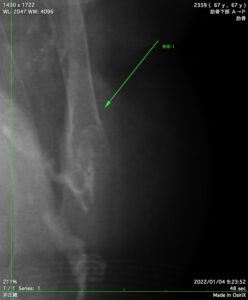

爪が巻き込まないようにに支えているのは爪の両端先端部分です。

その為、爪の端を切り込むと支えが無くなり、爪が丸まって趾に食い込みます。巻き爪です。

巻き爪の人はほとんど切りすぎです。